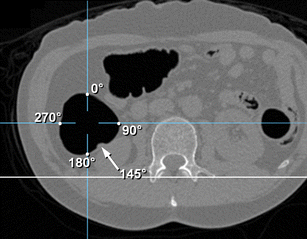

A search of our CTC and colonoscopy database found 37 patients (43 eligible lesions) who fulfilled the following criteria: colonoscopy-proven sessile polyps ≥6 mm in the straight mid-ascending colon, lesion visualisation in both supine and prone CTC, and optimal colonic distension. A coordinate system was developed to designate the polyp radial location (°) along the luminal circumference, unaffected by rotation of the torso. The degree/direction of polyp radial location change (i.e. ascending colonic rotation) between supine and prone positions correlated with anthropometric measurements.

Movement from supine to prone positions resulted in a change in the radial polyp location of between −23° and 79° (median, 21°), demonstrating external rotation of the ascending colon in almost all cases (2° to 79° in 36/37 patients and 42/43 lesions). The degree/direction of rotation mildly correlated with the degree of abdominal compression in the anterior-posterior direction in prone position (r = 0.427 [P = 0.004] and r = 0.404 [P = 0.007]).

The ascending colon was usually found to rotate externally as patients moved from supine to prone positions, partly dependent on the degree of abdominal compression.